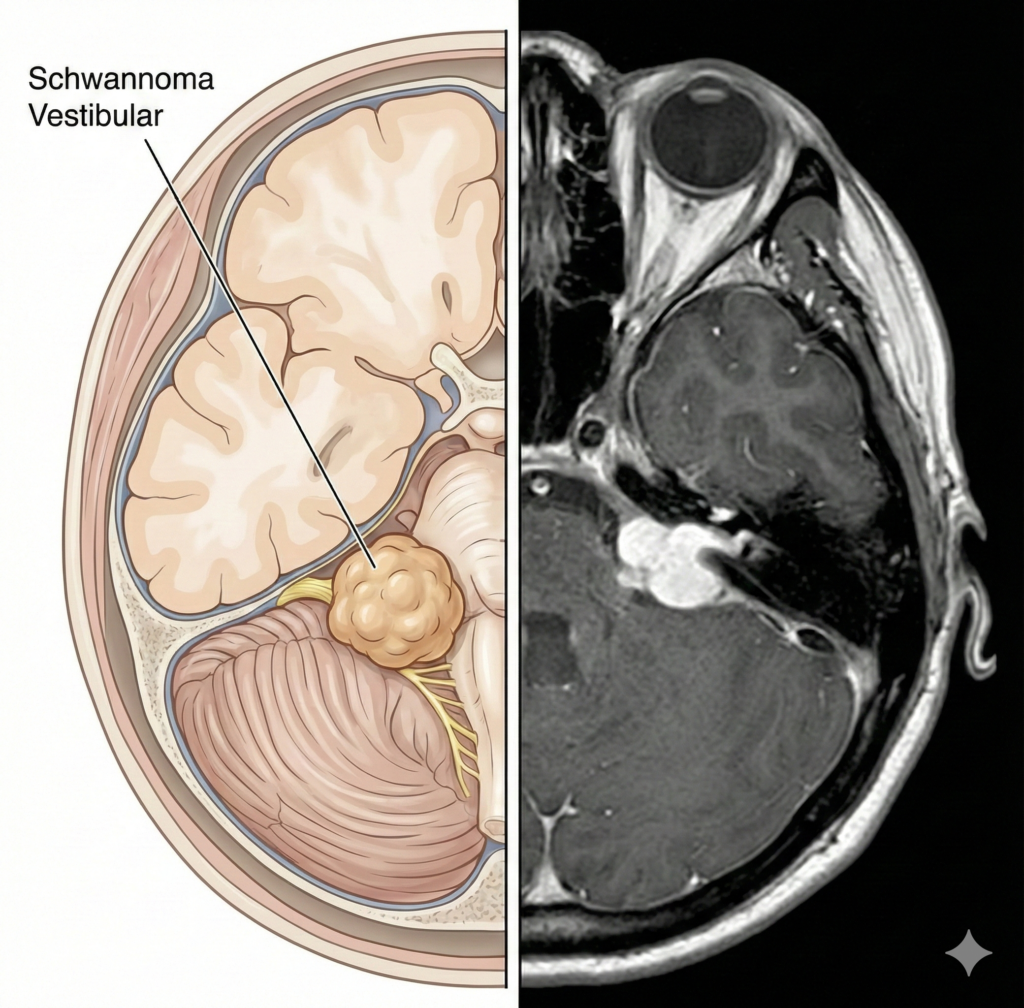

SÍNTOMAS

¿Qué síntomas

pueden aparecer?

- Pérdida auditiva progresiva en un solo oído

- zumbidos (tinnitus)

- problemas de equilibrio

*En tumores grandes puede haber debilidad facial.*

DIAGNÓSTICO

¿Cuál es el siguiente paso?

Resonancia magnética con contraste y pruebas de audición (audiometría).

EVOLUCIÓN

¿Cómo será mi evolución?

Seguimiento

Las opciones incluyen observación, radiocirugía para tumores pequeños/medianos o microcirugía si hay crecimiento o síntomas graves.

Objetivo

El objetivo quirúrgico es preservar el nervio facial.